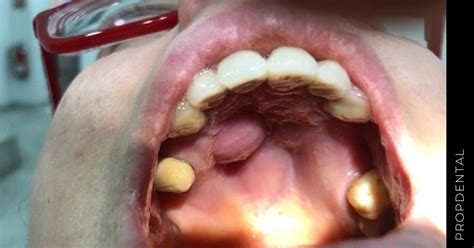

Un bulto en el paladar es una protuberancia o masa que aparece en la parte superior de la boca. Estos bultos pueden tener distintos tamaños, formas y consistencia diferentes, y pueden ser tanto blandos o duros si los presionamos. Aunque la mayoría de los bultos en el paladar son benignos, algunos pueden indicar problemas más serios los cuales requieren de una atención médica urgente.

La señal para saber si nuestro paladar goza de buena salud es fijarnos en que tenga un color rosáceo uniforme. Si descubrimos irritaciones, bultos o inflamación general, pueden ser indicativos de padecer algún tipo de enfermedad bucodental.

Los bultos en el paladar pueden ser duros o blandos, dolorosos o no dolorosos, y pueden aparecer y desaparecer. Es importante examinar el color, la forma, localización y dureza del bulto en el paladar.